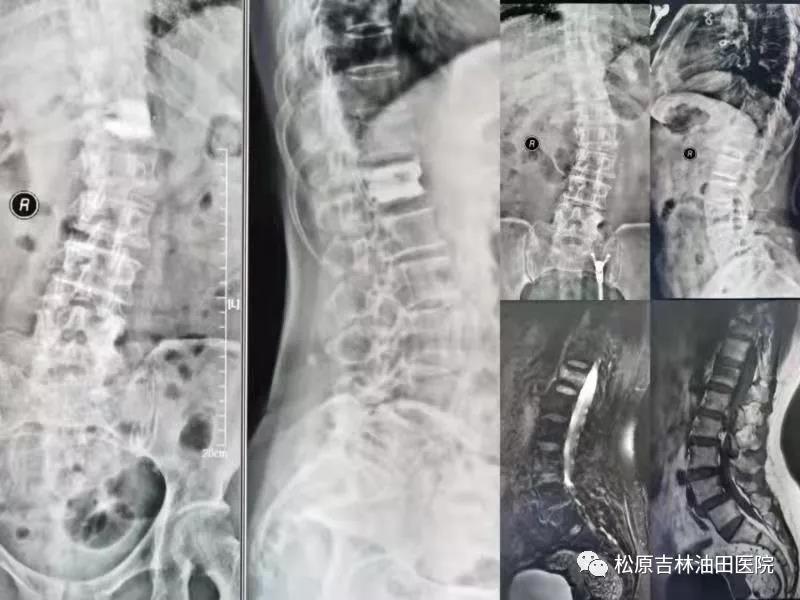

90岁老爷爷术前影像显示:腰1椎体压缩性骨折

90岁老爷爷术后影像显示:骨水泥良好的弥散和支撑